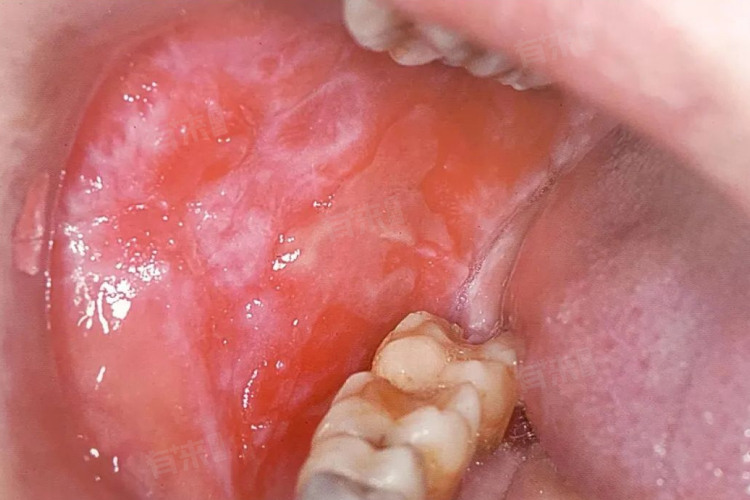

1、口腔黏膜白色斑纹

斑纹的形态多样,可以是网状、树枝状或斑块状等。网状斑纹就像一张细密的网覆盖在口腔黏膜上;树枝状的斑纹则像树枝的分支一样,有主干和分支;斑块状斑纹表现为白色的、边界相对清晰的斑块,大小不一。